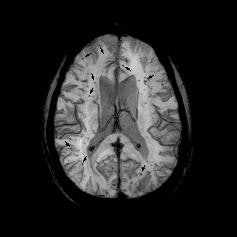

Researchers from the University of California, Irvine have observed cerebral microbleeds on MRI brain scans that indicate a blood vessel tear may not always be the cause of blood deposits, according to a study published online September 6 in Frontiers in Cellular Neuroscience.

Previous research has shown that MRI can detect cerebral microbleeds in approximately 20% of people by age 60 and 40% of people by age 80.